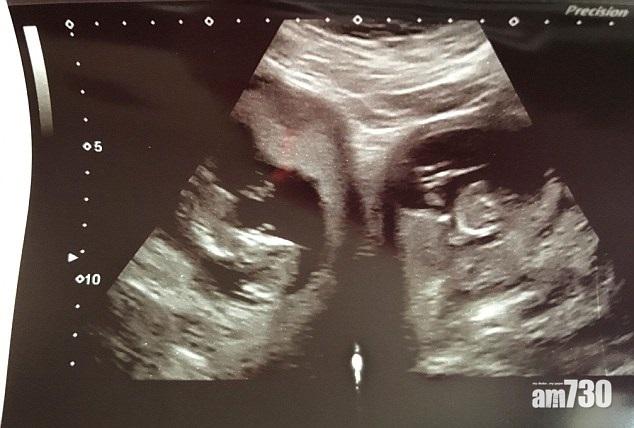

曼徹斯特女生Ebony Stevenson(18歲)去年12月初忽感不適,遂就寢休息,其後被母親發現情況不妙速送院,證實出現妊娠毒血症,須施以人工昏迷及即時剖腹分娩。她於數天後醒來,驚見床畔躺著親骨肉:7磅半的女嬰!院方解釋這宗罕有個案,指Ebony有兩個子宮,胎兒則由一個隱藏子宮孕育,沒有出現妊娠特徴不足為奇;又指她僅得一邊輸卵管有效,意味不容易受孕,能順利孕懷及誕下B女,這倒是萬幸。